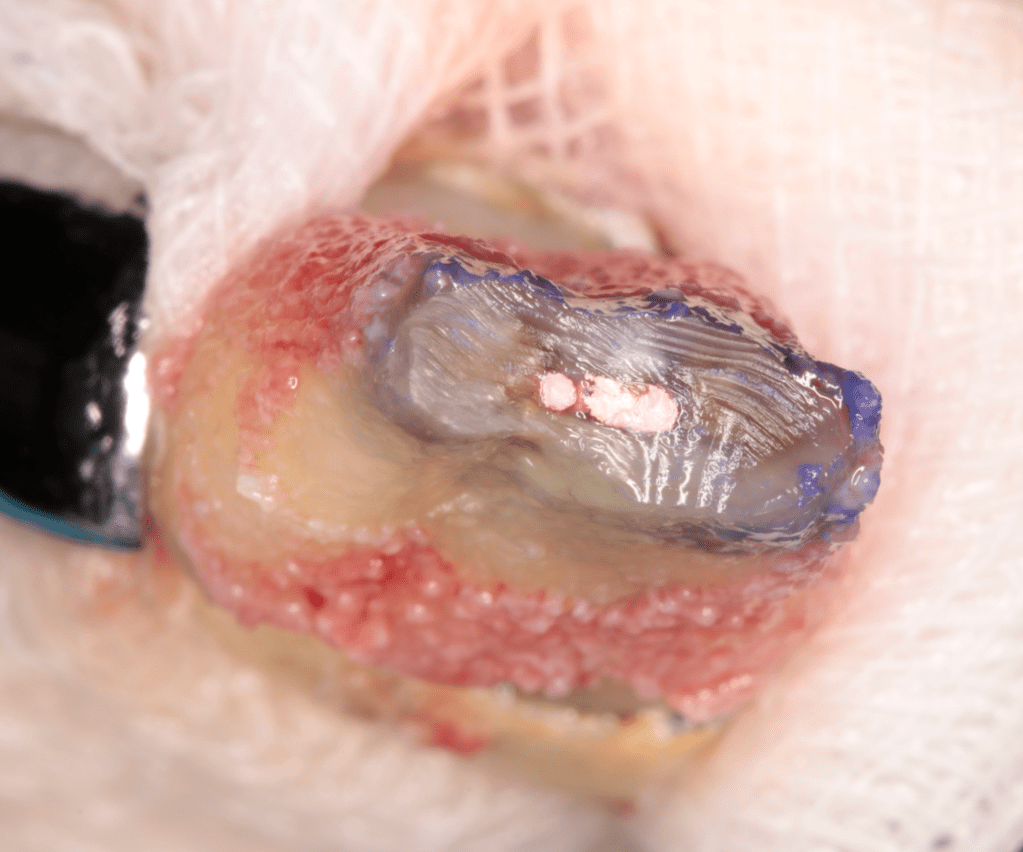

Autotansplantes

REIMPLANTES

Intencional por dificil acceso coronal y quirúrgico

Reinplante por fracaso de tratamiento

Reimplante, istmo apical, curación cortical palatina 1 año